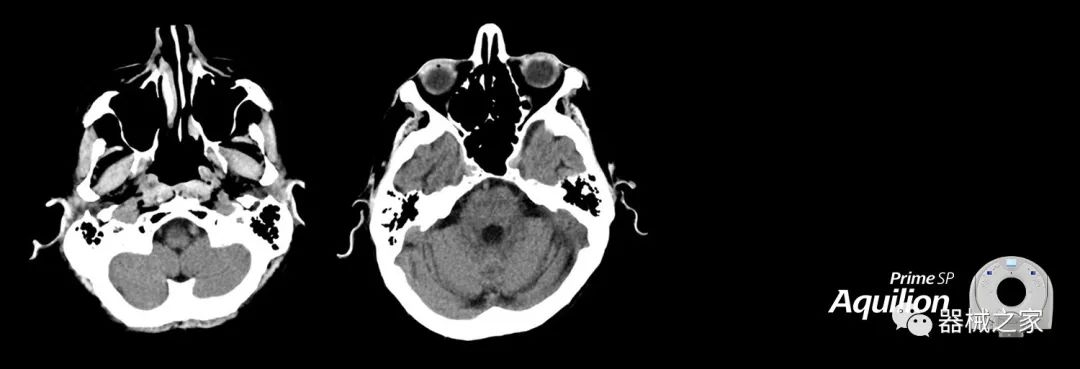

Aquilion Prime SP使設(shè)施能夠處理具有挑戰(zhàn)性的案例,同時為員工提供快速,靈活和高效的解決方案。

兩個CT系統(tǒng)均采用0.5 mm x 80排PUREViSION探測器技術(shù)(可配置并從80-160現(xiàn)場升級),78 cm孔徑,50 cm視野,AIDR(自適應迭代劑量減少)3-D和SEMAR(單個)能量金屬神器減少)技術(shù)。